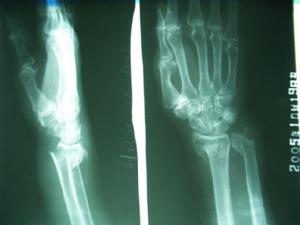

肱骨投擲骨折是由扭曲力和拉張力共同作用所致的螺鏇形不穩定骨折。其特徵是骨折近側段內鏇移位而遠側段外鏇移位,造成斷端間的鏇轉分離。如患者受傷後為減輕疼痛而將前臂托起抱於胸前,則遠側骨折段的外鏇畸形常有部分代償。同時由於上臂肌肉的牽引作用骨折遠段常有上移,造成上臂短縮畸形由於骨外膜僅發生縱形撕裂和掀起,未完全橫斷,故對骨折端的側方移位仍有束縛作用,側方移位不大由於走行於後外側的橈神經在骨膜之外,不容易卡入骨折端,因此神經損傷機會較少但如出現骨折側方較大錯位,骨折斷端骨膜破裂,骨折的尖端可頂於橈神經幹上,致使神經損傷。

可結合外傷史、症狀、體徵及X線片,但需注意檢查是否有橈神經損傷及其他合併傷的體徵。

X線檢查,可顯示患肢骨折且多呈螺鏇形。